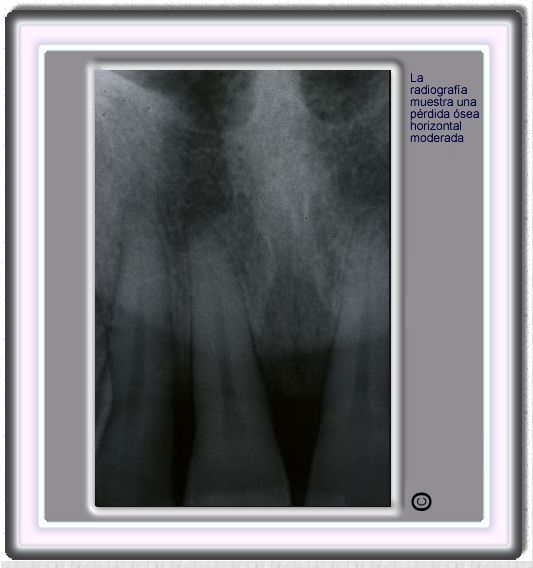

image 548